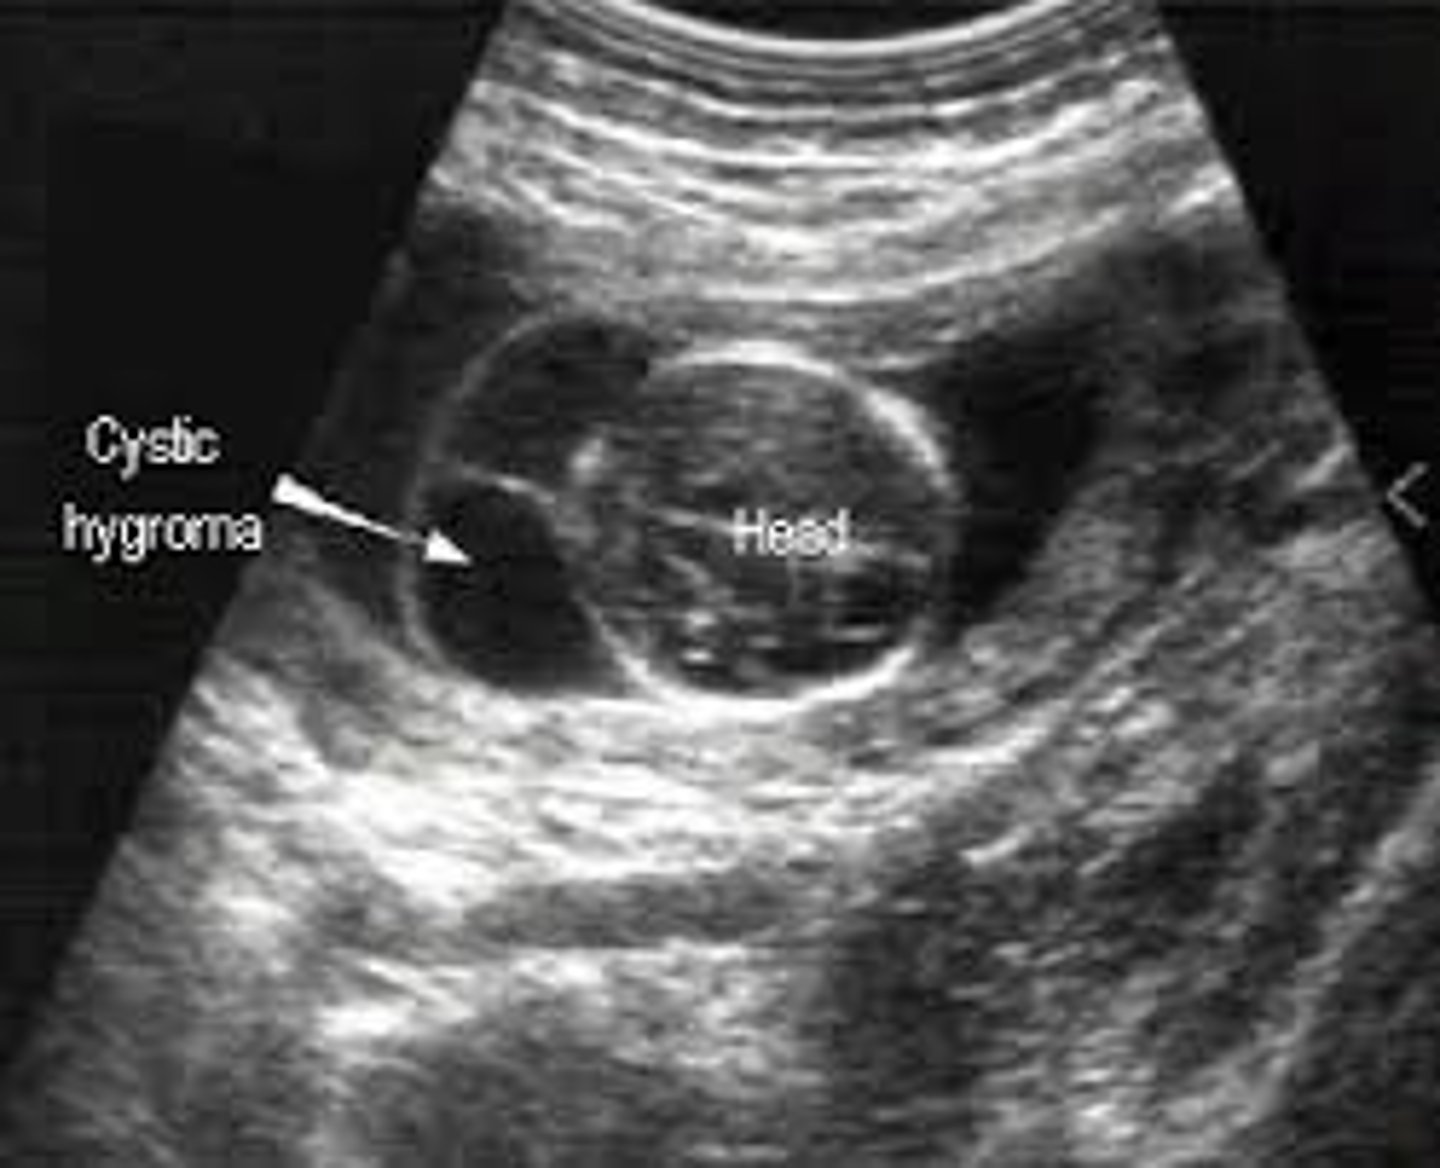

Cystic Hygroma

Most common neck mass

Abnormal connection of lymphatic vessels

Associated with Turner's syndrome & aneuploidies

Features of Turner's Syndrome in a Fetus

Horseshoe kidneys

Turner's Syndrome

Absent X chromosome or 46X0/46XXX

Trisomy 13